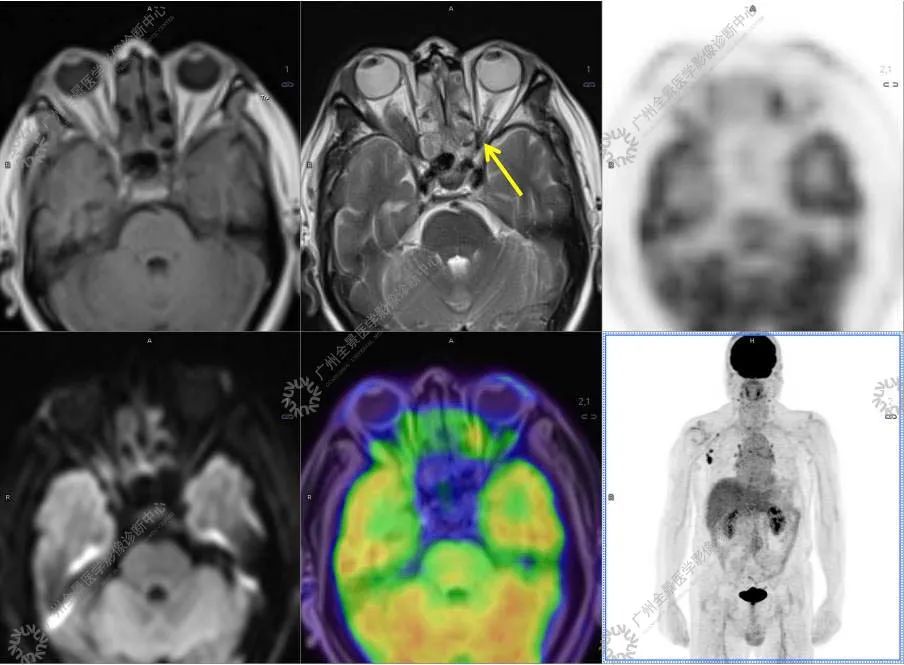

●18FDG-PET/CT 作为一种解剖和功能结合新的显像方法,IgG4-RD 的诊断及鉴别诊断中存在着巨大的优势:

●18FDG 对于炎性病变的检出有很高的敏感性, 但特异性较差,结合 CT 解剖影像可以明显的提高诊断的准确率。

●对于因各种原因无法进行增强检查的患者,特别是肾功能受损的患者, 18FDG-PET/CT 可以作为一种很好的替代方法,几乎不对肾功能产生任何影响。

●18FDG-PET/CT 扫描作为一种全身检查,有着传统影像学局部扫描无法比拟的优势,PET/CT 扫描不仅可以发现以临床症状为导向的局部病灶,更可以发现远隔部位的受累病灶。

结合影像及实验室检查,临床最终考虑 IgG4 相关性疾病。